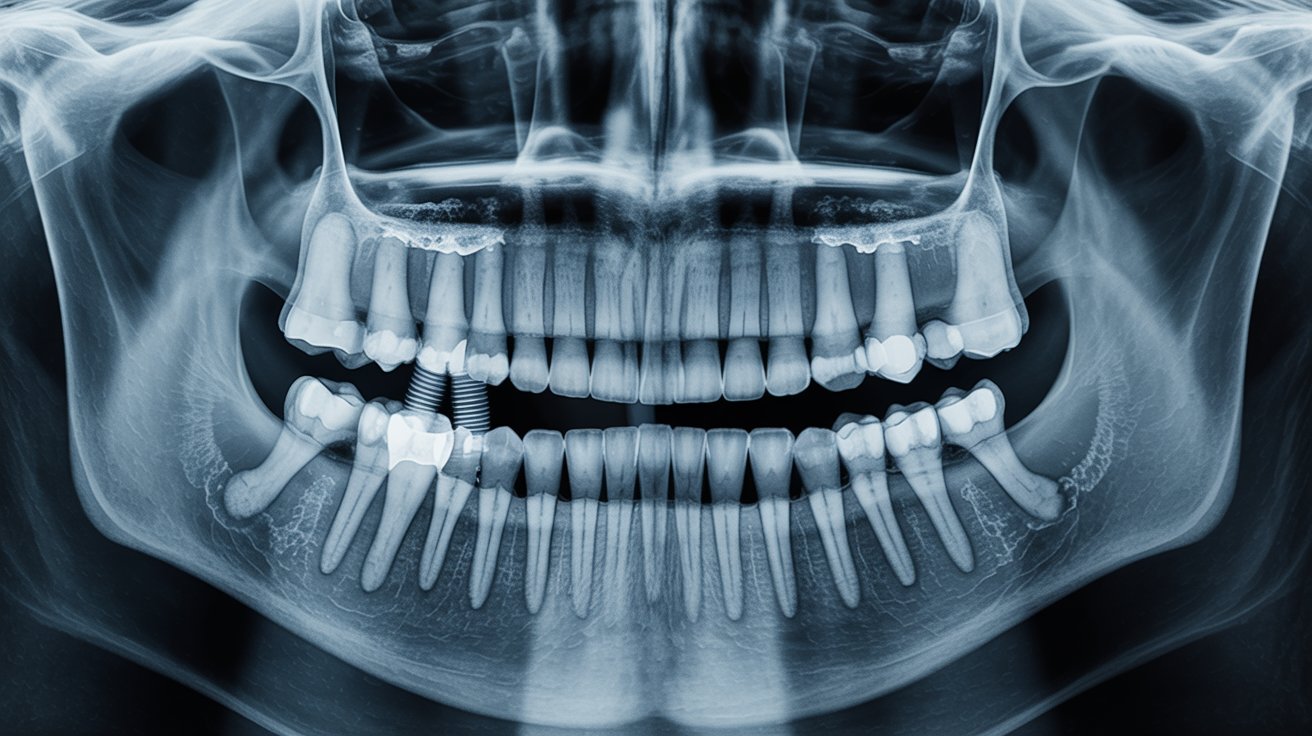

Traditional implants are placed into the jawbone and are ideal when you have adequate bone volume and density. When the upper jaw has resorbed (shrunk) substantially, conventional implants may first require sinus lifts or bone grafting, adding cost and time. Zygomatic implants are longer implants that engage the zygomatic bone (cheekbone)—a denser anchor—so clinicians can restore the upper arch even when the maxillary bone is too thin or soft for standard implants without major augmentation.

Zygomatic placement requires advanced imaging (CBCT), careful mapping of sinus and zygomatic anatomy, and a surgeon experienced with long, angled trajectories to the cheekbone. This specialized skillset and longer operating time contribute to higher fees.

Zygomatic fixtures are longer and often require custom or premium components and multi-unit abutments engineered for full-arch alignment. These devices cost more than typical endosteal implants.